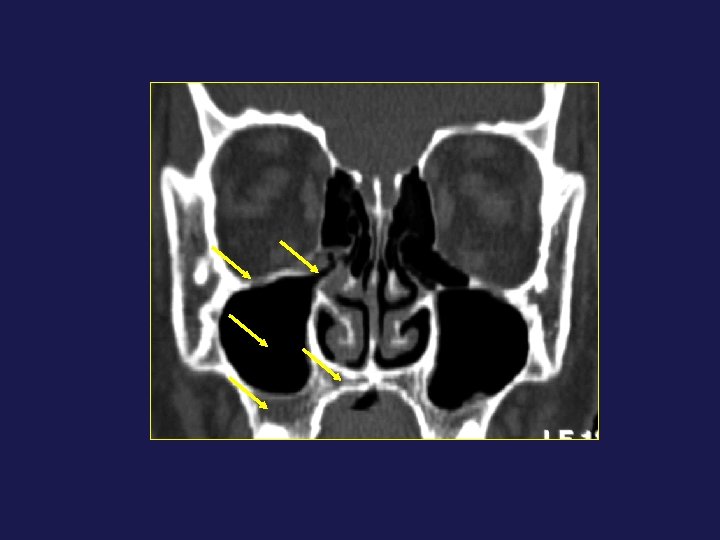

QUESTIONS DU CHIRURGIEN ? • Confinement mécanique • Risque chirurgical

QUESTIONS DU CHIRURGIEN ? • Confinement mécanique

• Risque chirurgical : – Hémorragique – Lésion du nerf optique – Fuite

• Risque chirurgical : – Hémorragique – Lésion du nerf optique – Fuite du LCR